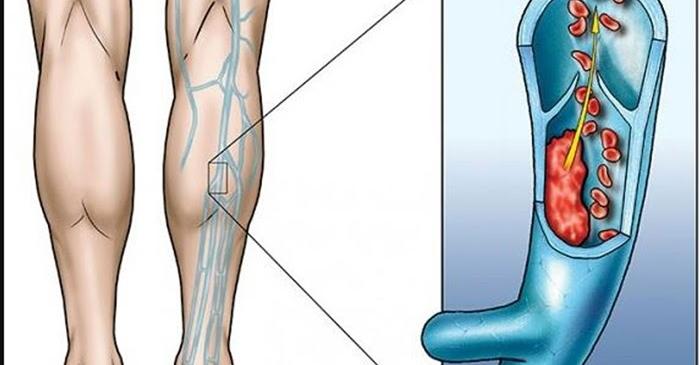

Нарушеното кръвообращение може да доведе до сериозни здравословни проблеми Ако

Ако страдате от спукани капиляри или разширени вени знаете че

...... лечение. Имайте предвид, че кръвообращението е много важен аспект на вашето здраве и признаците за влошаването му в никакъв случай не трябва да бъдат пренебрегвани.